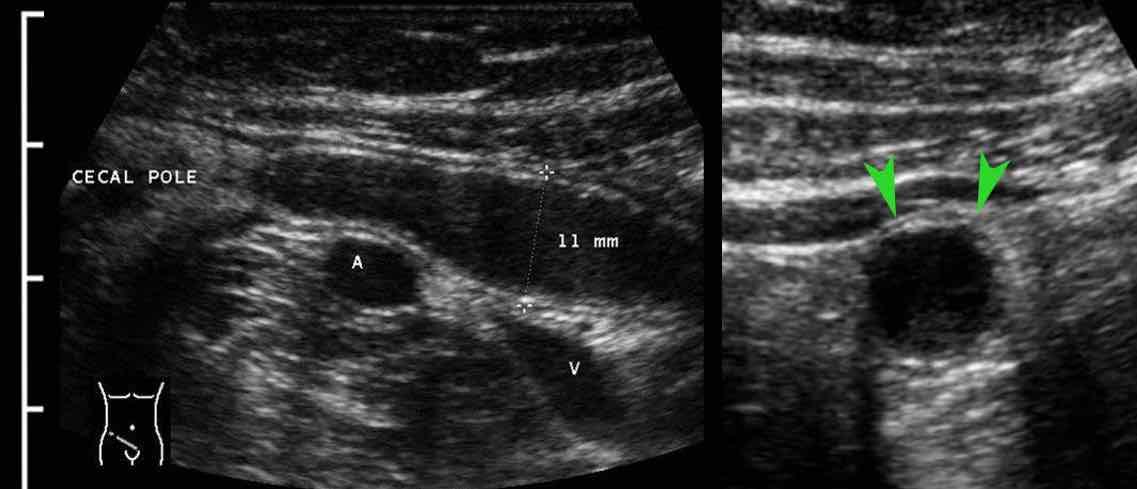

Viêm ruột thừa với sỏi phân trong lòng ruột thừa (mũi tên) được tìm thấy tại vị trí tắc nghẽn (a và v = động mạch và tĩnh mạch chậu).

Hình ảnh điển hình của ruột thừa viêm:

- mất nhu động

- cấu trúc phân lớp đồng tâm

- không thể ép xẹp

- đầu tận cùng bịt kín

- cấu trúc hình xúc xích

- ở vị trí cố định, thường tại vị trí đau tối đa

- đường kính tối đa trung bình là 11 mm (dao động từ 6 đến 25 mm)

- trong 35% trường hợp, sỏi phân trong lòng ruột thừa (mũi tên) được tìm thấy tại vị trí tắc nghẽn

Trong 6-12 giờ đầu, lòng ruột thừa giãn rộng rõ rệt với thành mỏng và chưa có hiện tượng viêm mô mỡ xung quanh.

Bệnh nhân này nhập viện với cơn đau quanh rốn dữ dội, cấp tính kéo dài 4 giờ và không có đau khu trú tại vị trí ruột thừa giãn (giai đoạn đau tạng).

Lưu ý hiện tượng phồng của ruột thừa căng vào thành bụng (đầu mũi tên) trong khi ép.